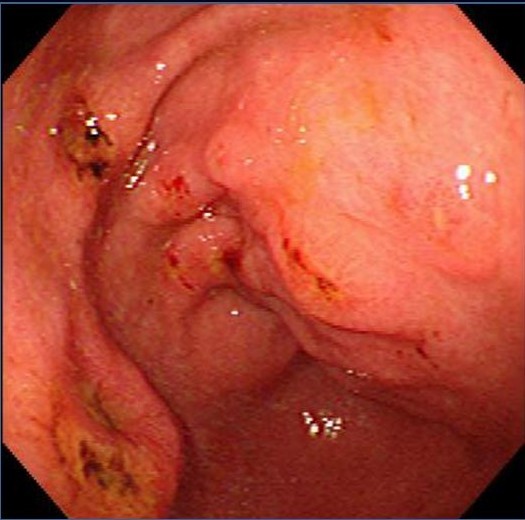

福州台江医院医师指出:慢性糜烂性胃炎患者的胃黏膜出现多个疣状、膨大皱襞状或丘疹样隆起,直径5~10mm,顶端可见黏膜缺损或脐样凹陷,中心有糜烂,隆起周围多无红晕,但常伴有大小相仿的红斑,以胃窦部多见,可分为持续型及消失型,这些病灶是无法通过目测的,需要借助当今胃镜检查,才能仔细观察出来。台江医院医师指出:慢性糜烂性胃炎患者的胃黏膜出现多个疣状、膨大皱襞状或丘疹样隆起,直径5~10mm,顶端可见黏膜缺损或脐样凹陷,中心有糜烂,隆起周围多无红晕,但常伴有大小相仿的红斑,以胃窦部多见,可分为持续型及消失型,这些病灶是无法通过目测的,需要借助当今胃镜检查,才能仔细观察出来。

急诊内镜检查:在出血后的一两天内作急诊内镜检查,可见以多发性糜烂和出血灶为特征的急性胃黏膜病变,有确诊价值。